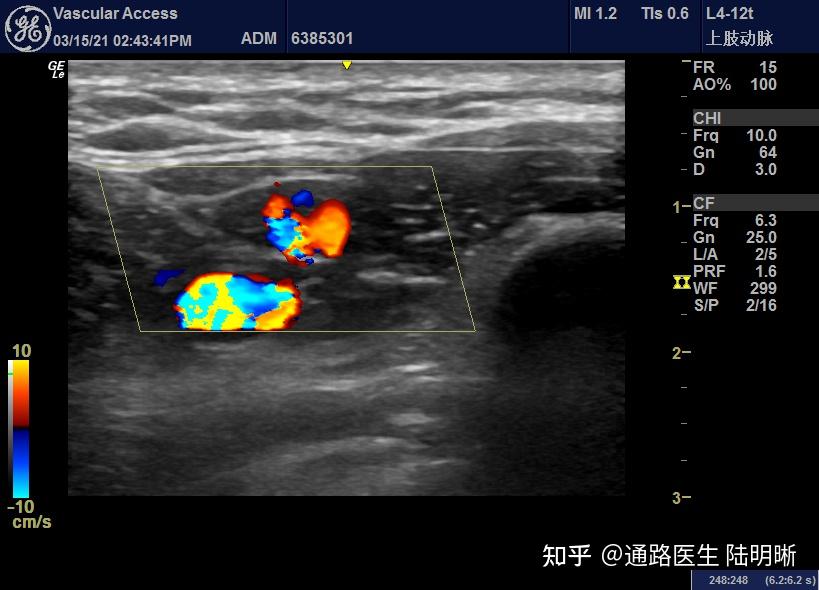

内瘘术后3月,成熟不良,头静脉转位位置狭窄,术前狭窄位置超声血流图

图片尺寸2667x2000